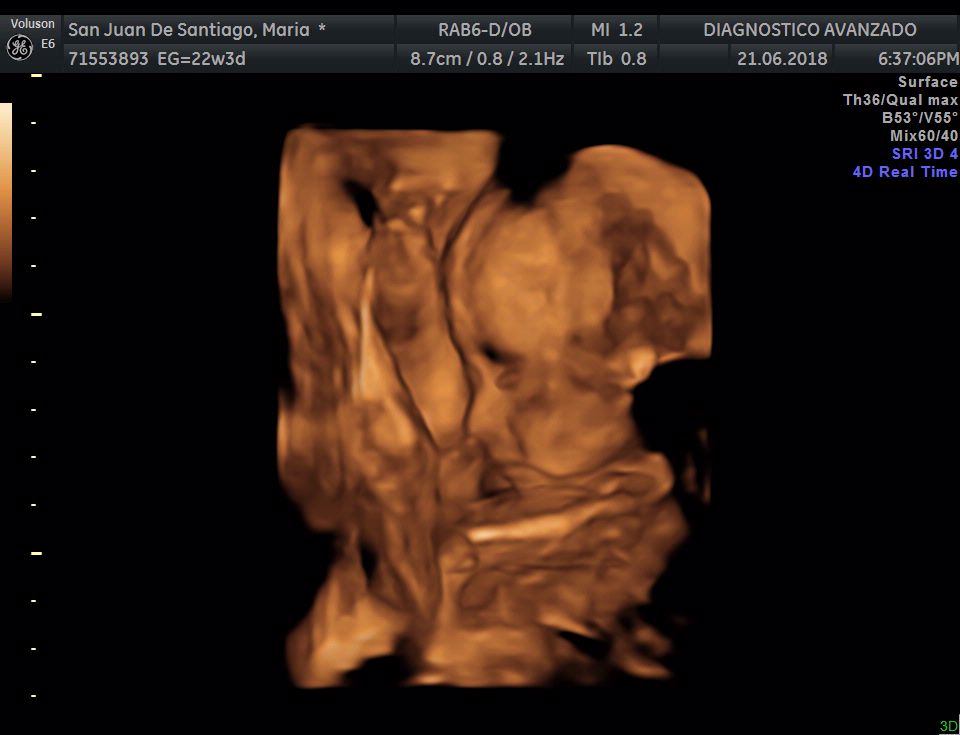

¡Hola a todos! Hoy hemos ido a hacer la tradicional ecografía 3D de la niña, os dejamos todo el material (aunque es un poco demasiado).